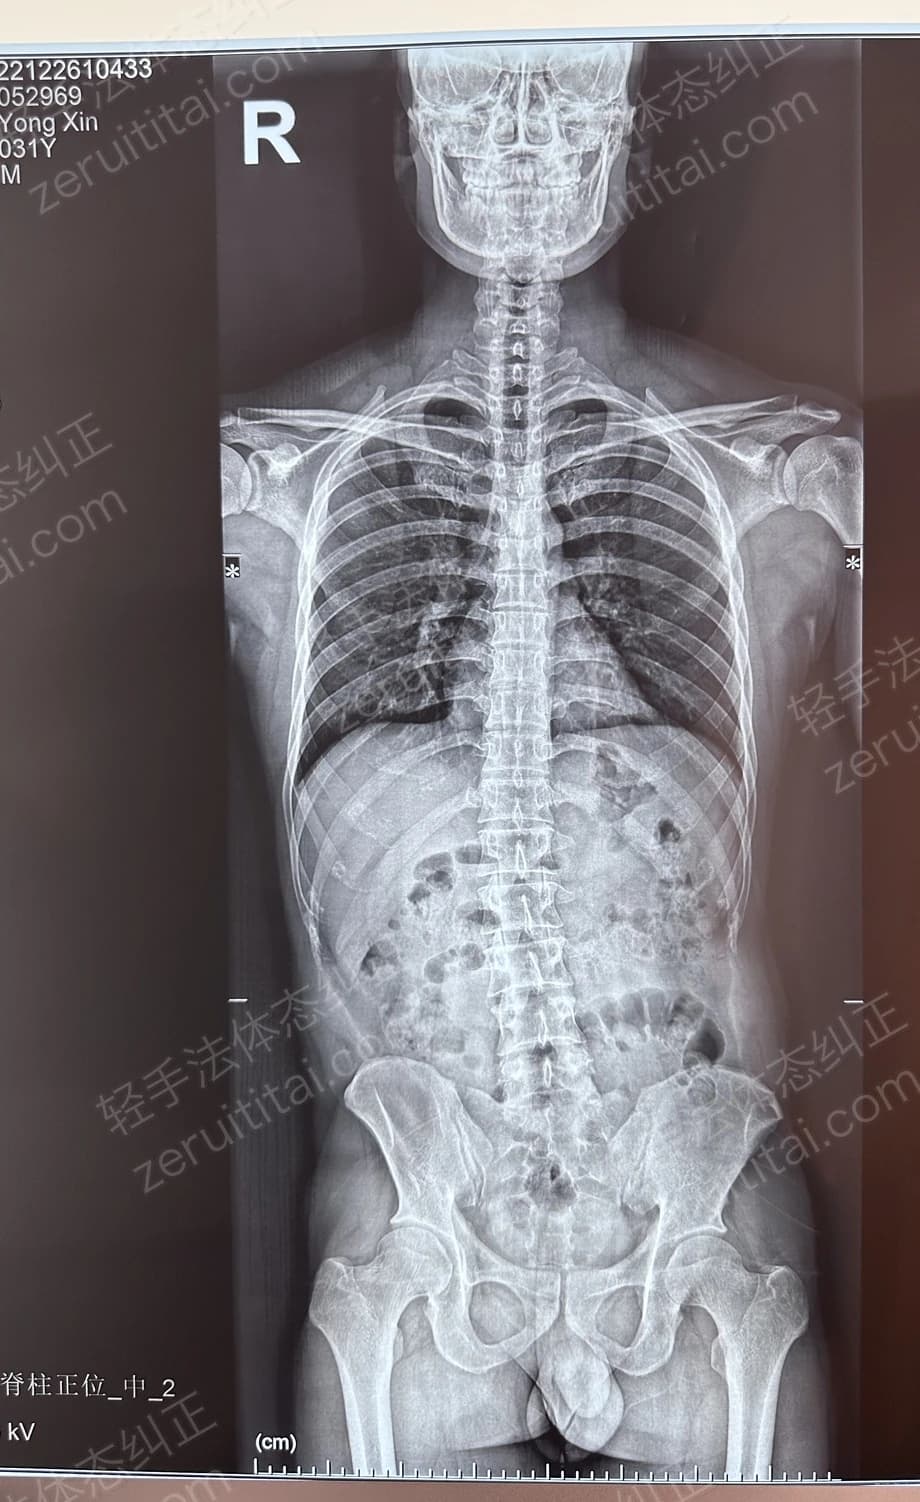

2022.06.27

第 1 次记录

第 1 次记录2022.06.27

正面 X 光